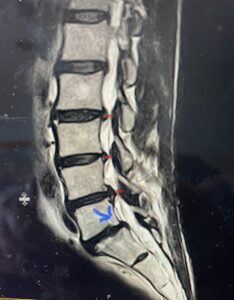

(Fig. 2) T2-weighted lumbar MRI demonstrating severe lumbar stenosis (red markers) and a grade 1 spondylolisthesis at L5-S1 (blue arrow)

Because she had failed conservative management of her lumbar stenosis and spondylolisthesis it was decided to perform a lumbar laminectomy and fusion of the L5-S1 segment. Because of her history of severe osteoporosis and hardware cut-out from the bone, we decided to offer her hydroxyapatite-coated screws to provide fixation of her L5-S1 segment (Fig. 4a and b)

Intraoperatively, we noticed that with the aid of these special screws we got good fixation with the hope that over the next 6 months there would be excellent osteointegration of the screws because of the coating of hydroxyapatite. She had an uneventful postoperative course with improvement of her leg symptoms.